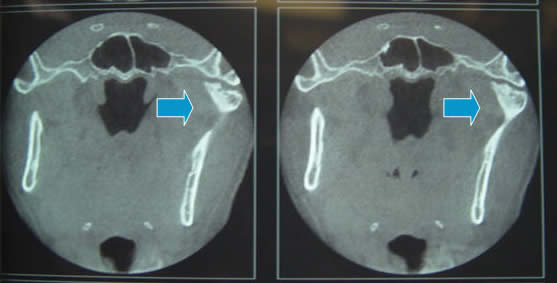

11.7.3 ข้อต่อขากรรไกรเคลื่อน(หลุด) (Temporomandibular joint dislocation)

ข้อต่อขากรรไกรเคลื่อน(หลุด)

หรือที่ผู้ป่วยไทยมักเรียกว่า กรามค้าง หรือ ขากรรไกรค้าง อาจเรียกอีกอย่างว่า

open-lock หรือ luxation เป็นสภาพ

ที่คอนดายล์เคลื่อนไปอยู่หน้าต่อปุ่มหน้าแอ่งข้อต่อขากรรไกร

(articular eminence) และไม่สามารถกลับคืนสู่แอ่งข้อต่อขากรรไกร (temporomandibular

fossa) ได้ อาการทางคลินิกที่เห็นได้ชัด คือผู้ป่วยไม่สามารถหุบปากได้

เกณฑ์การวินิจฉัย

- ไม่สามารถหุบปากได้ เว้นแต่จะมีวิธีการช่วยจับข้อต่อขากรรไกรให้เข้าที่

- ภาพถ่ายรังสี พบคอนดายล์วางตัวหน้าต่อปุ่มแอ่งกระดูกข้อต่อขากรรไกร